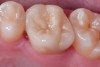

An example of this material subcategory is lithium disilicate (eg, IPS e.max®, Ivoclar Vivadent), a glass ceramic material composed of silica, lithium dioxide, alumina, potassium oxide, and phosphorous pentoxide. After the crystalline component has reached optimal growth through the manufacturing process, it is pulverized into powder and processed through a variety of different techniques.22 Lithium disilicate is indicated for the same clinical situations as other glass ceramics; however, when fabricated to a full-contour, monolithic restoration and seated with resin cement, it is also appropriate for higher stress situations, such as those requiring full crowns, even on molars (Figure 9 through Figure 11).

New additions to the category are zirconia-reinforced lithium silicates (ZLSs) (eg, VITA Suprinity®, Figure 12; CELTRA™ Duo, Dentsply Sirona). ZLS materials comprise a lithium silicate glass ceramic that is strengthened with approximately 10% zirconia crystals. Although these materials are new to the market as of press time, initial in vitro testing shows they have excellent optics and physical properties similar to lithium disilicates. Only lithium disilicates have long-term clinical data to support their use as single restorations anywhere in the mouth, however.

Restorations fabricated from this material subcategory demonstrate high strength, fracture resistance, and natural-looking esthetics,23 yielding a versatile and strong alternative for a wider variety of indications. They are indicated when higher risks are involved (eg, less than 50% enamel remains on the tooth, less than 50% of the bonded substrate is enamel, and/or when 30% or more of the margin is in dentin).

Due to the material's glass properties, adhesive bonding is recommended. However, bonding to dentin results in less predictable restorations due to dentin's flexibility; restorations bonded to enamel are much more predictable, given enamel's significant stiffness compared to dentin.19

Fig 9. Preoperative view (Fig 9), preparation with composite block-out restoration (Fig 10), and final cementation of CL-IIb material (Fig 11) (final ceramic contour and stain by Steve Lee, CDT, MDC).

Figure 9

Fig 10. Preoperative view (Fig 9), preparation with composite block-out restoration (Fig 10), and final cementation of CL-IIb material (Fig 11) (final ceramic contour and stain by Steve Lee, CDT, MDC).

Figure 10

Fig 11. Preoperative view (Fig 9), preparation with composite block-out restoration (Fig 10), and final cementation of CL-IIb material (Fig 11) (final ceramic contour and stain by Steve Lee, CDT, MDC).

Figure 11